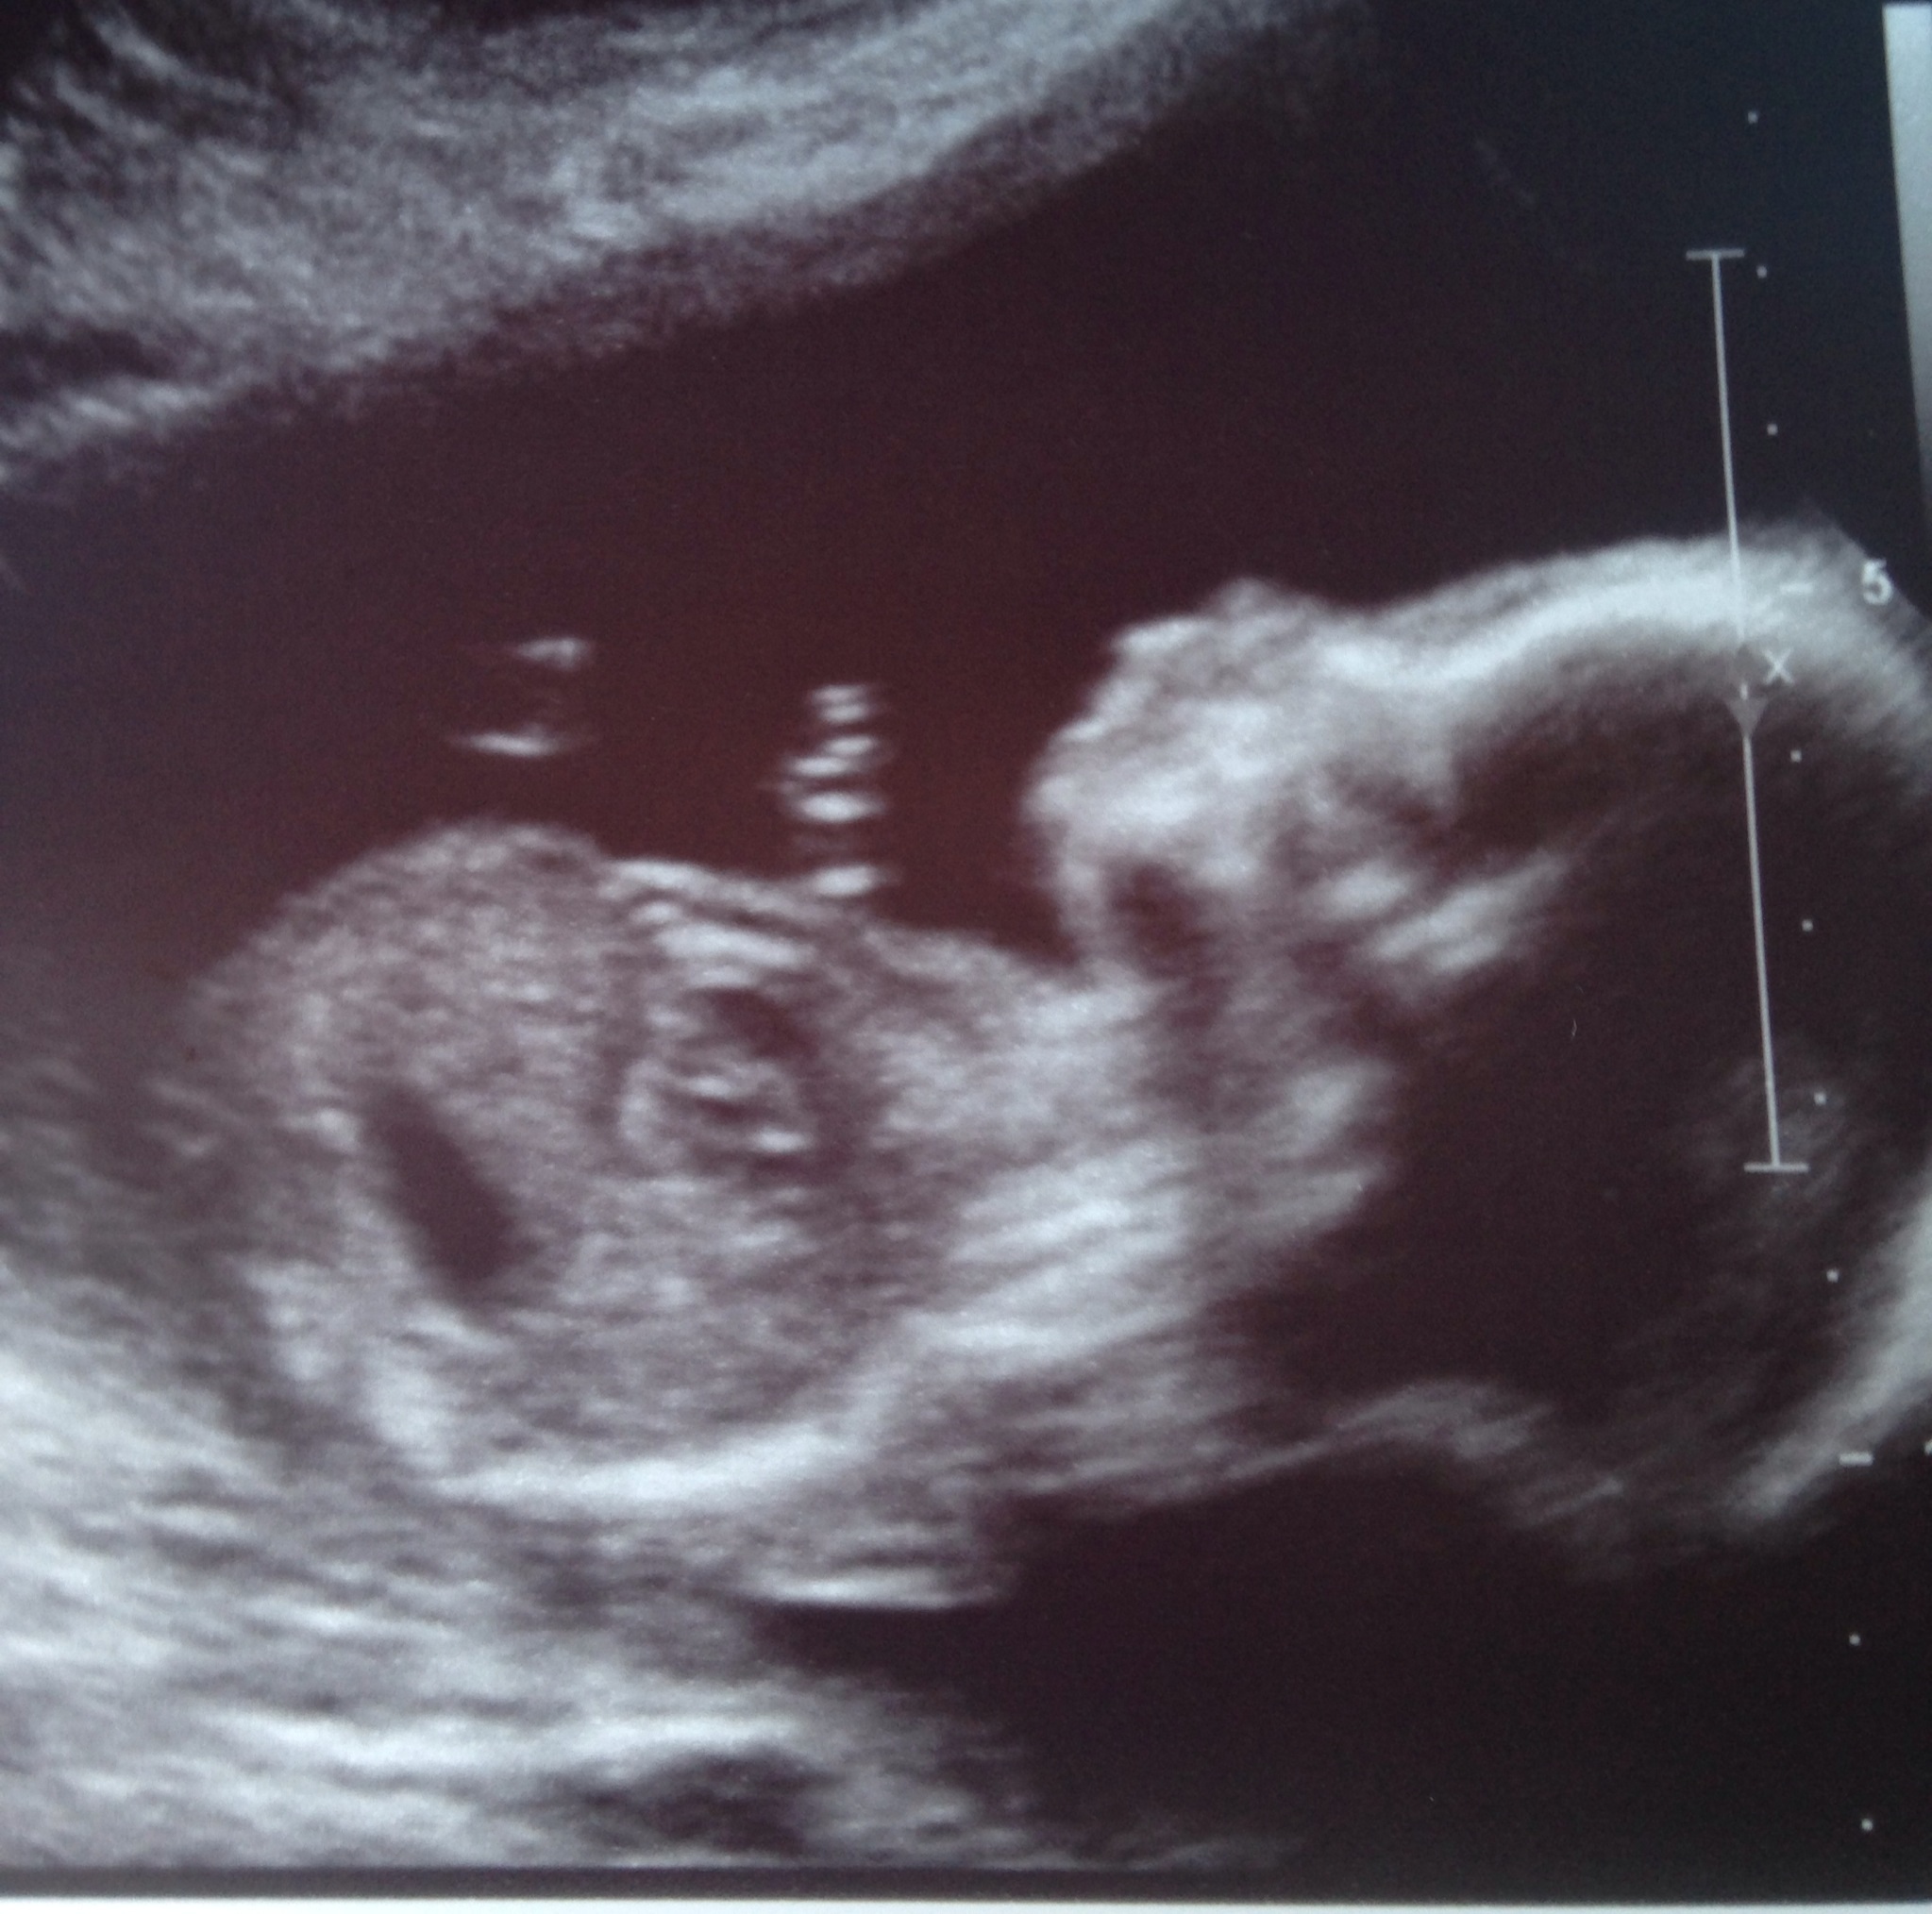

image

Married my love 10/18/08 | DS born 07/16/11 | MMC 01/16/13 at 11w6d | DD edd 04/27/14

• YAY! Love seeing these updates! Congrats ladies. I hope I didn't miss anyone - if I did, tag me! :)